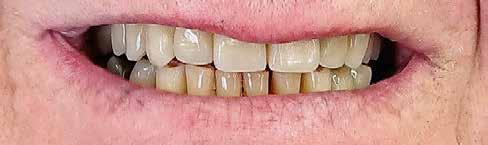

2015-ben egy 47 éves férfi páciens állkapocs-ízületi panaszai miatt kereste fel a rendelőnket. Ezen felül esztétikai problémát jelentett számára, hogy az egyik felső nagymetszőfogán lévő héj eltört (1-3. ábrák). A klinikai és radiológiai vizsgálatot követően megállapítható volt, hogy a páciens kifejezett bruxizmusa miatt csökkent a harapási magassága, és jelentős mennyiségű saját foganyagot abradált el (4. ábra)

8. ábra: Az őrlőfogak esetében nem volt szükség foganyag elvételre. Az alsó metszőfogak minimál invazív módon lettek előkészítve, a felső frontfogak esetében megőriztük az eredeti csiszolt csonkok formáját. 7. ábra: Két évvel később, a végleges helyreállítás megkezdése előtt készített felvétel (2017).